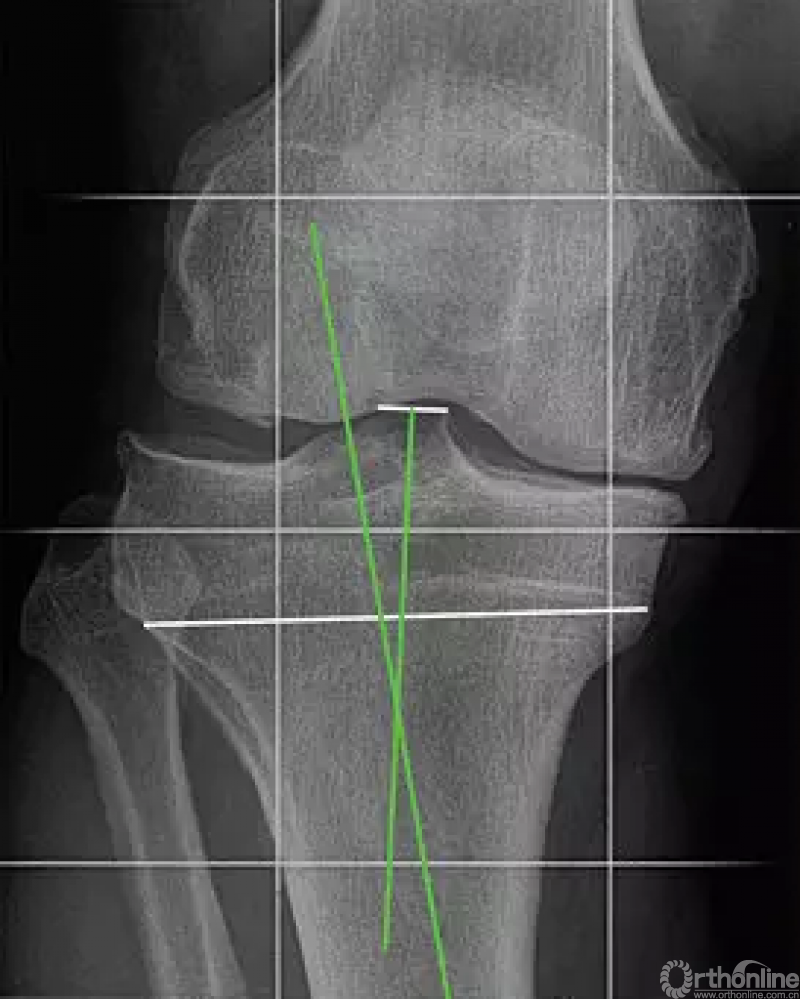

根据Bonnin和 Chambat的方法测量胫骨内翻角(TBVA)。测量方法是胫骨髁间棘的中点和残存的骨骺线的中点的连线与胫骨机械轴所成的夹角